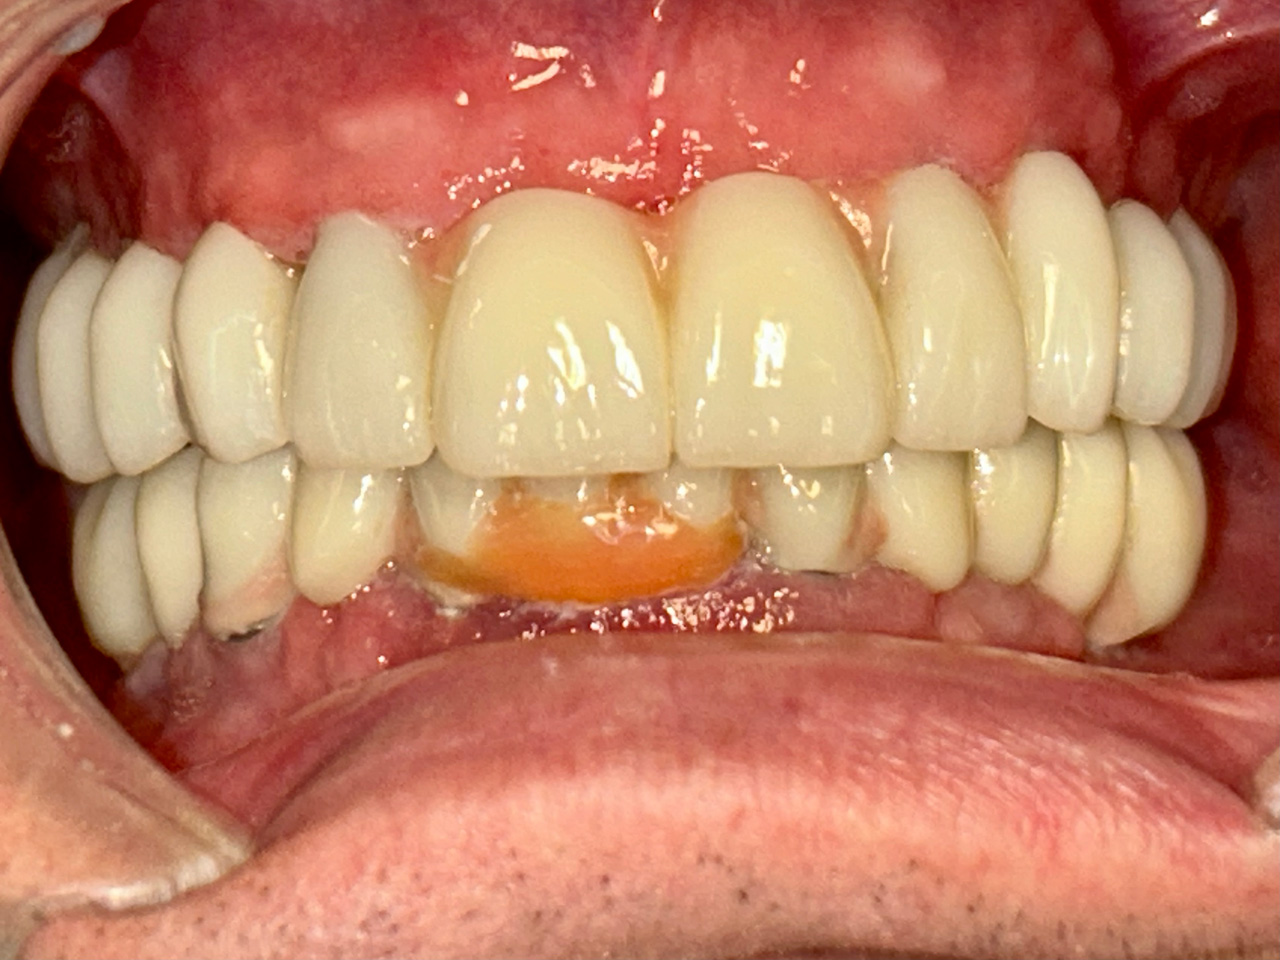

Teljes szájüregi rehabilitáció két lépésben

Ismét egy teljes szájüregi rehabilitáció két lépésben. Először az alsó fogak lettek kihúzva és azonnal implantálva, híddal ellátva, majd később a felső. IHDE svájci azonnal terhelhető implantátumok és cirkónium hidak. Dr. Kelemen Péter és a Symbion Fogtechnika közös munkája.